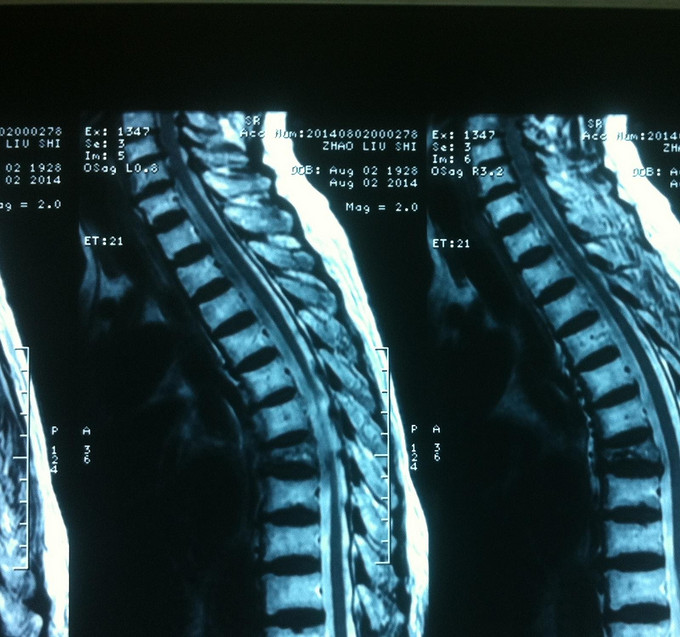

专科查体:背部后凸畸形,背部叩痛,腰骶部无叩痛,双下肢感觉无减退,双下肢肌力4-5级,双侧膝腱反射++,巴氏征阴性。影像学检查:X-Ray;骨质疏松、胸8楔形变。MR:胸8压缩性骨折,新鲜。